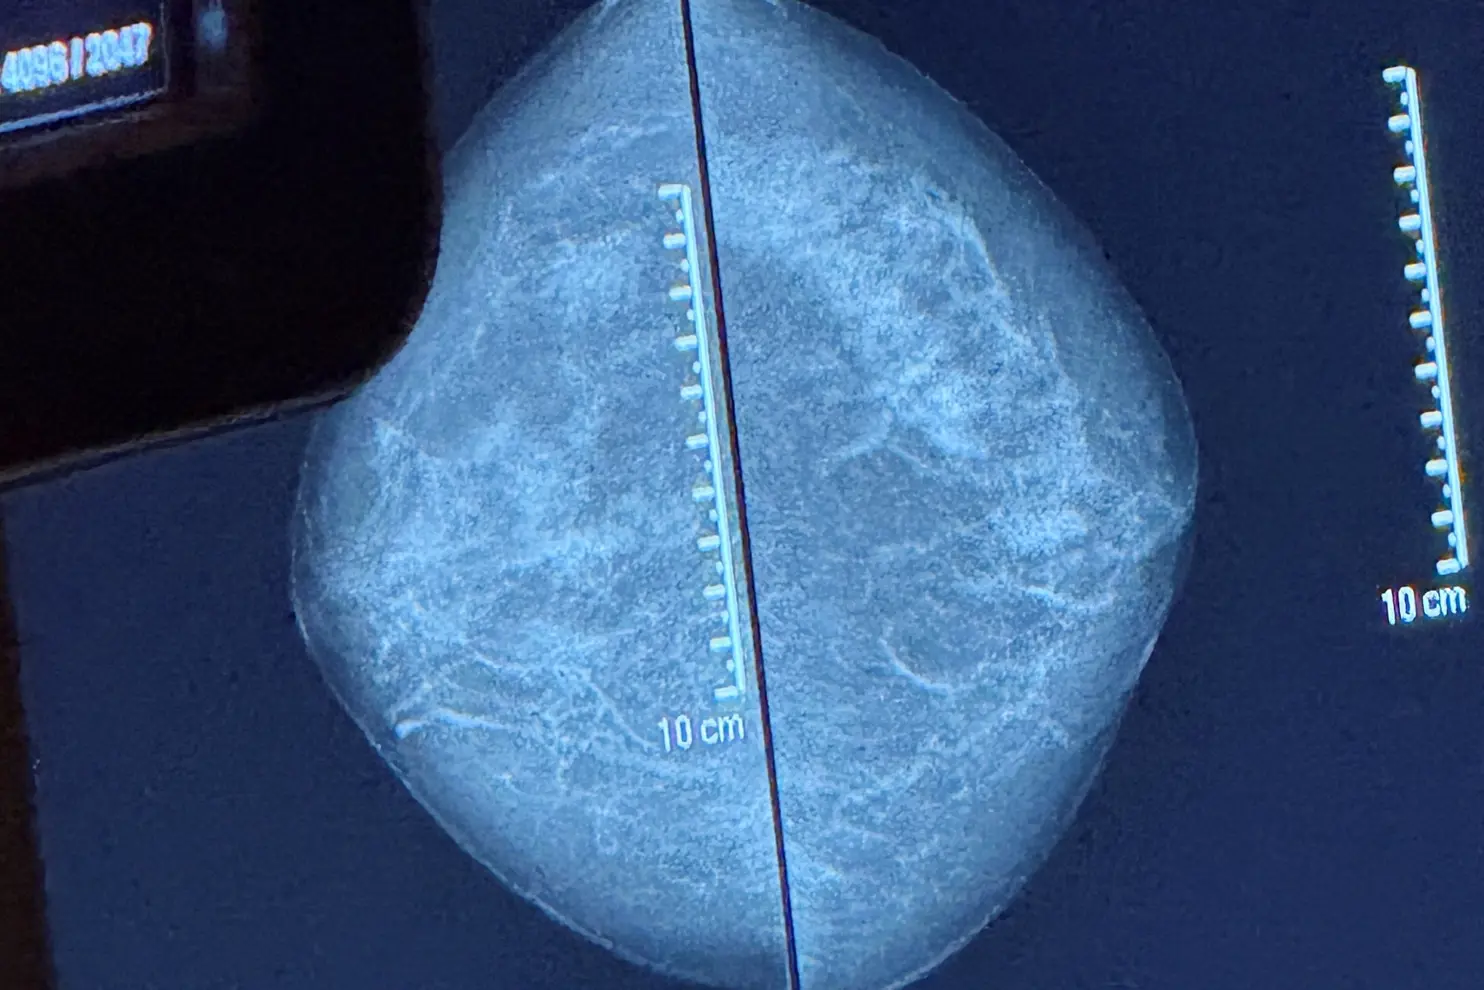

Screeningen inngår i det nasjonale mammografiprogrammet som tilbyr mammografi annethvert år til kvinner mellom 50 og 70 år. Målet er å oppdage brystkreft på et tidlig stadium og før sykdommen gir symptomer, for å øke sjansen for vellykket behandling.

I Norge er brystkreft den vanligste kreftformen blant kvinner, og omtrent 3.500 kvinner får diagnosen hvert år. Mammografiscreening har dokumentert effekt, og studier viser at programmet kan redusere dødeligheten i brystkreft med opptil 20 prosent blant kvinner som deltar regelmessig.

– Dette er en undersøkelse mange gruer seg for, og dere kommer svært tett på disse kvinnene med helt nødvendig berøring og fysisk posisjonering av brystene i apparatet. Det er fint å se den tryggheten og roen dere utviser, med stor empati og respekt, sier Alice Beathe.